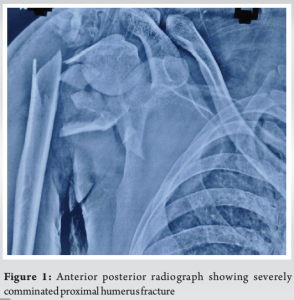

A 31-year-old male visited our outpatient department with complaints of right elbow pain on movement and restricted movements affecting his activities of daily living. He gave a history of road traffic accident 2 years before in which he had sustained a right-sided severely comminated proximal humerus fracture (Fig. 1) and right-side compound ulna proximal third shaft fracture with olecranon comminated fracture (Fig. 2). He underwent open reduction and fixation for proximal humerus (Fig. 3), olecranon and ulna fracture. 12 months post-surgery the proximal humerus implants were removed and the fracture was malunited (Fig. 4).